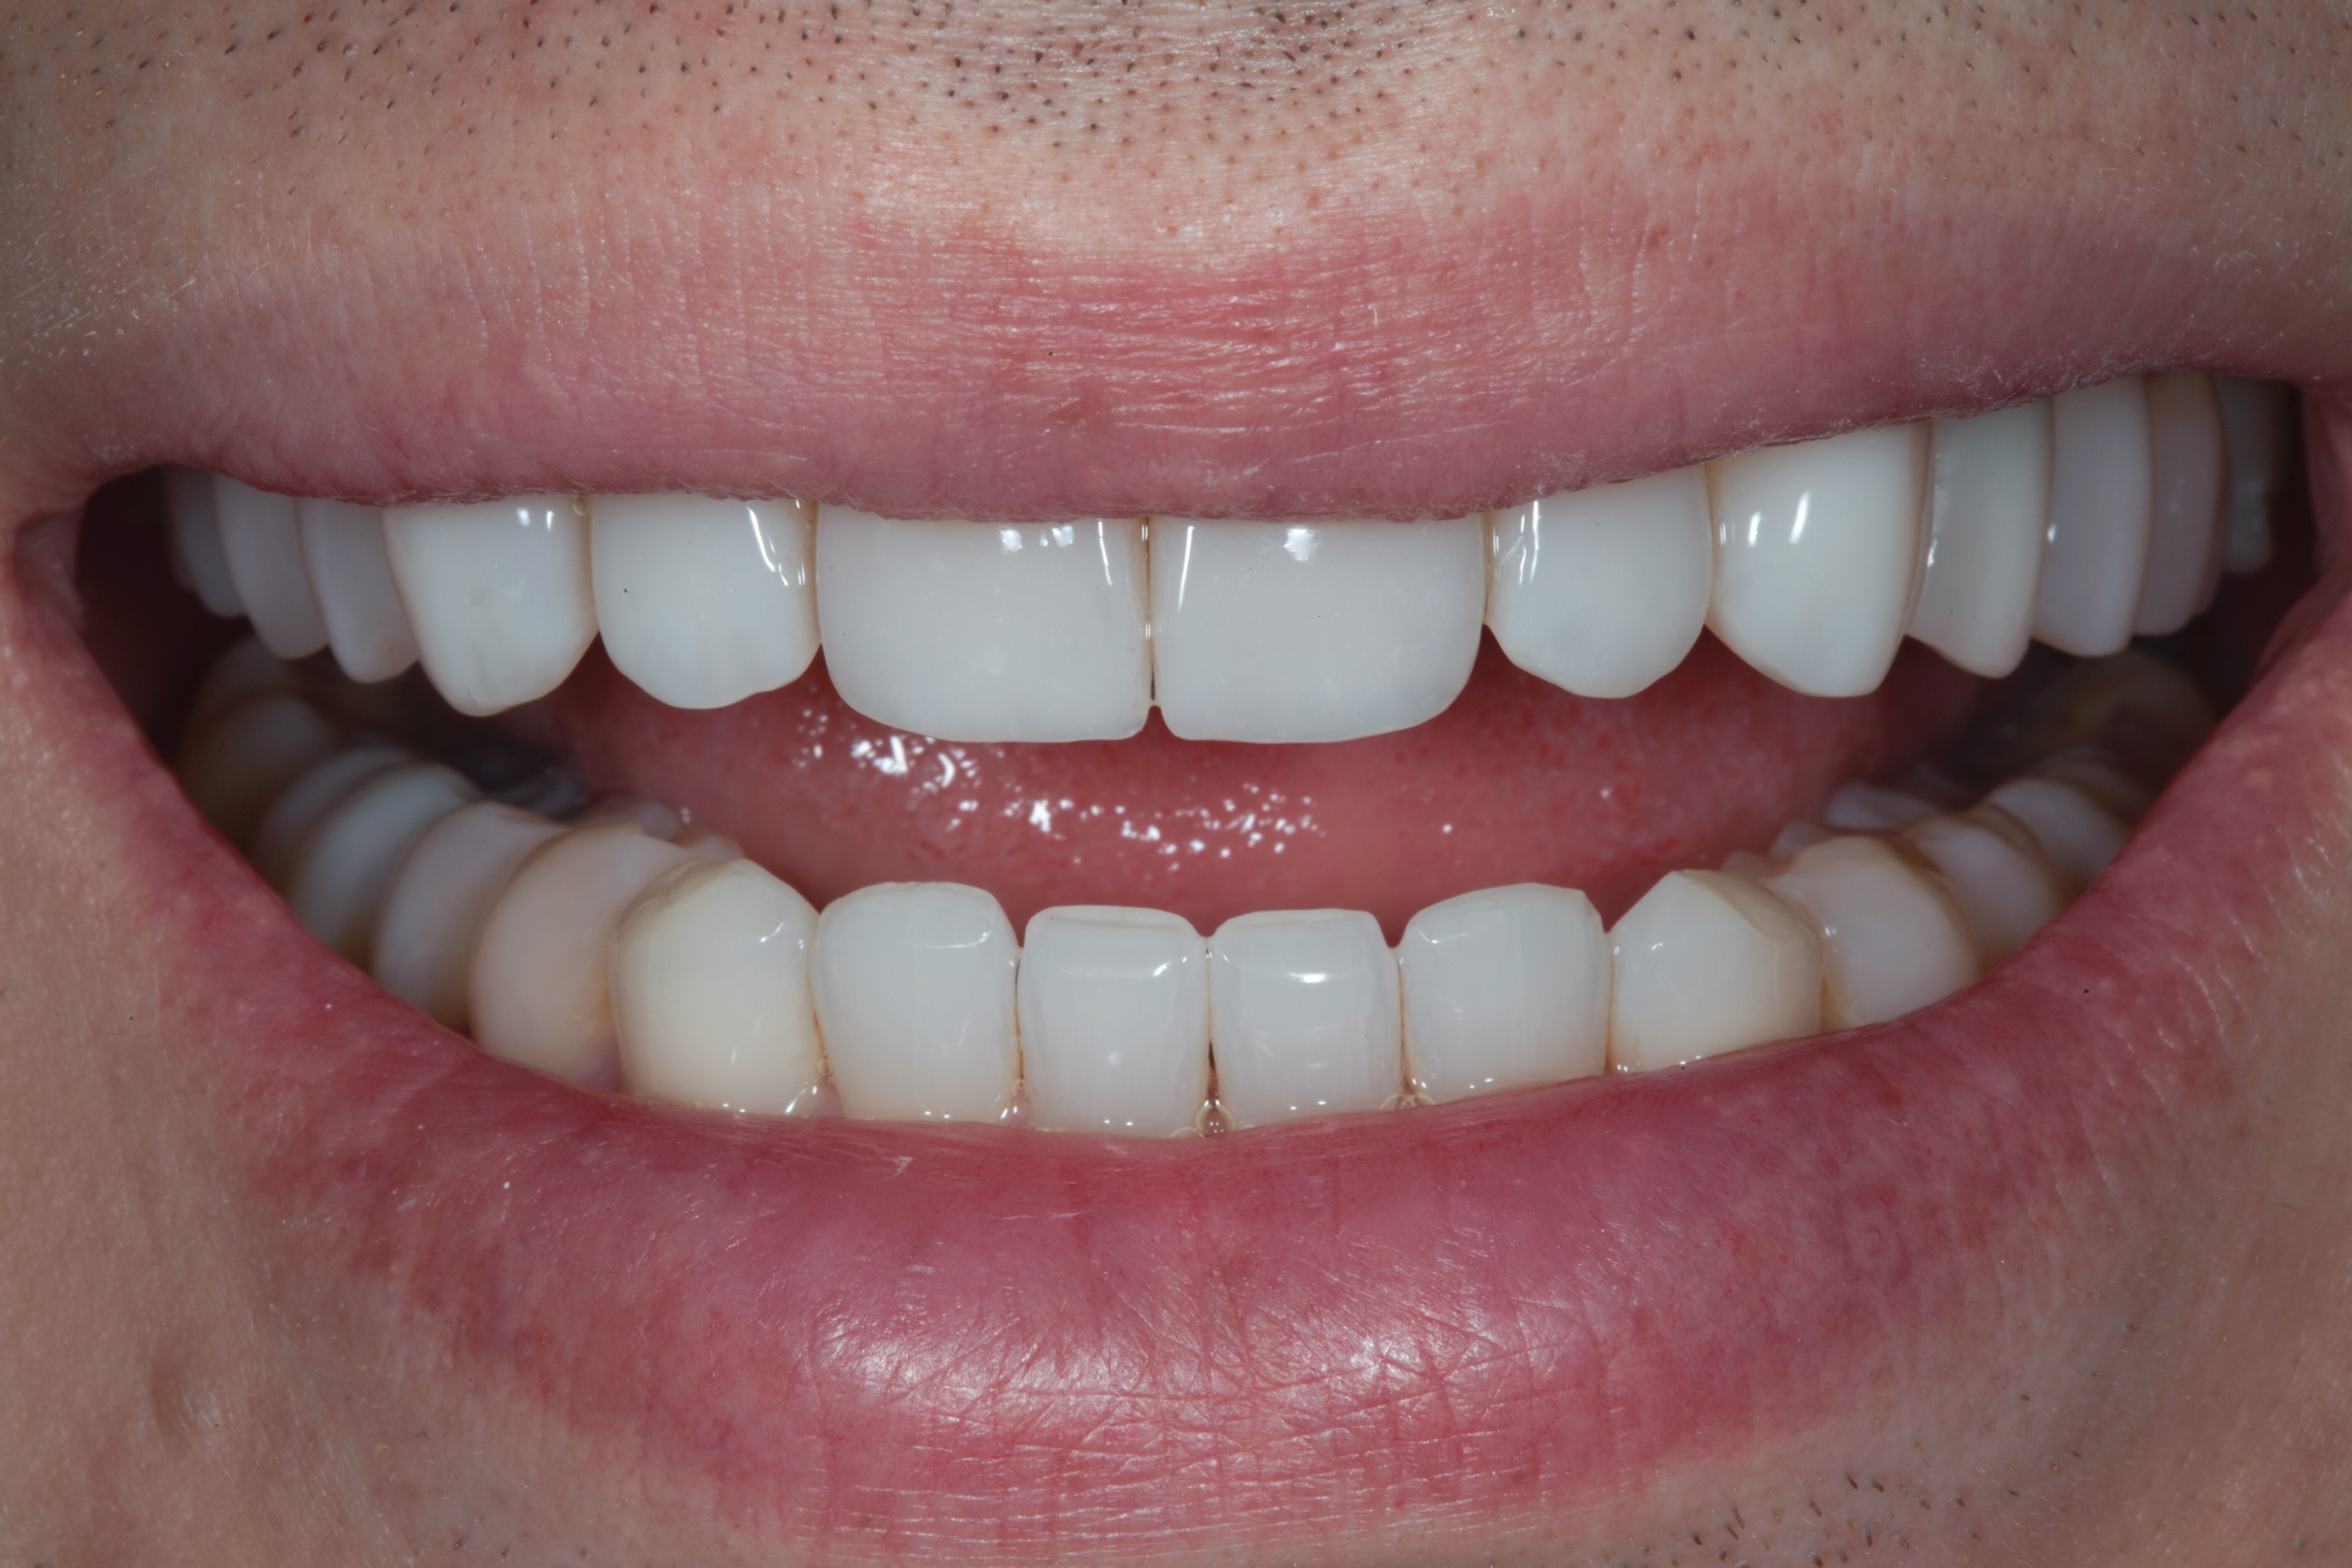

After the composite veneers were finalized, impressions were taken for a monolithic lithium disilicate crown on tooth No. 12. This was placed during a subsequent appointment, and occlusal equilibration was carried out. The patient returned for final photographs a couple of weeks later (Figure 10 through Figure 14).

(10.) Postoperative smile photograph.

Figure 10